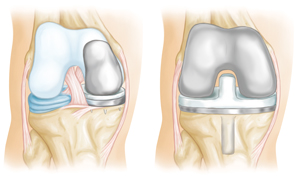

Total or partial knee replacement (arthroplasty). Your doctor will remove the damaged cartilage and bone, and then position new metal or plastic joint surfaces to restore the function of your knee.

(Left) A partial knee replacement is an option when damage is limited to just one part of the knee. (Right) A total knee replacement prosthesis.